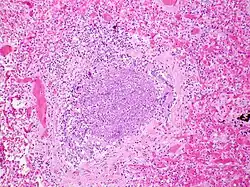

Bronchiolitis is most commonly caused by respiratory syncytial virus[7] (RSV, also known as human pneumovirus). Other agents that cause this illness include, but are not limited to, human metapneumovirus, influenza, parainfluenza, coronavirus, adenovirus, rhinovirus and mycoplasma.[12][13]